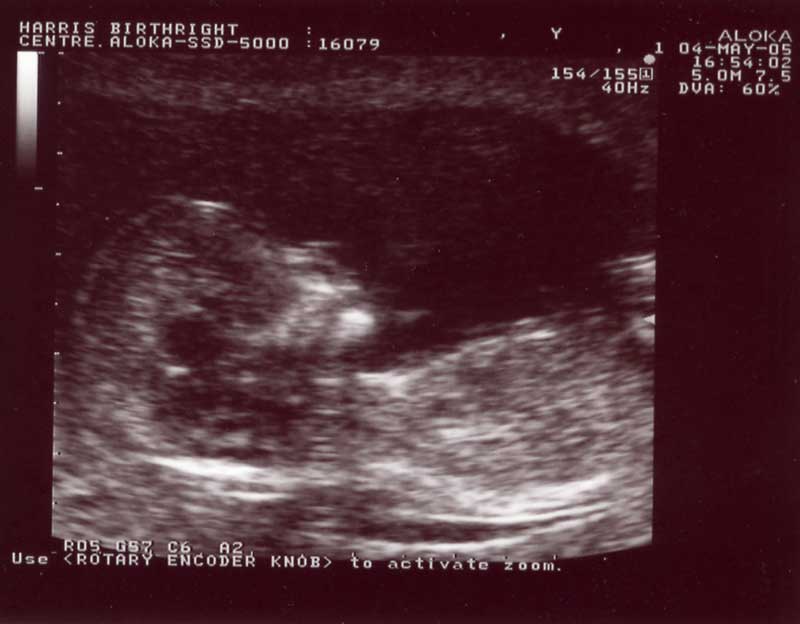

first scan